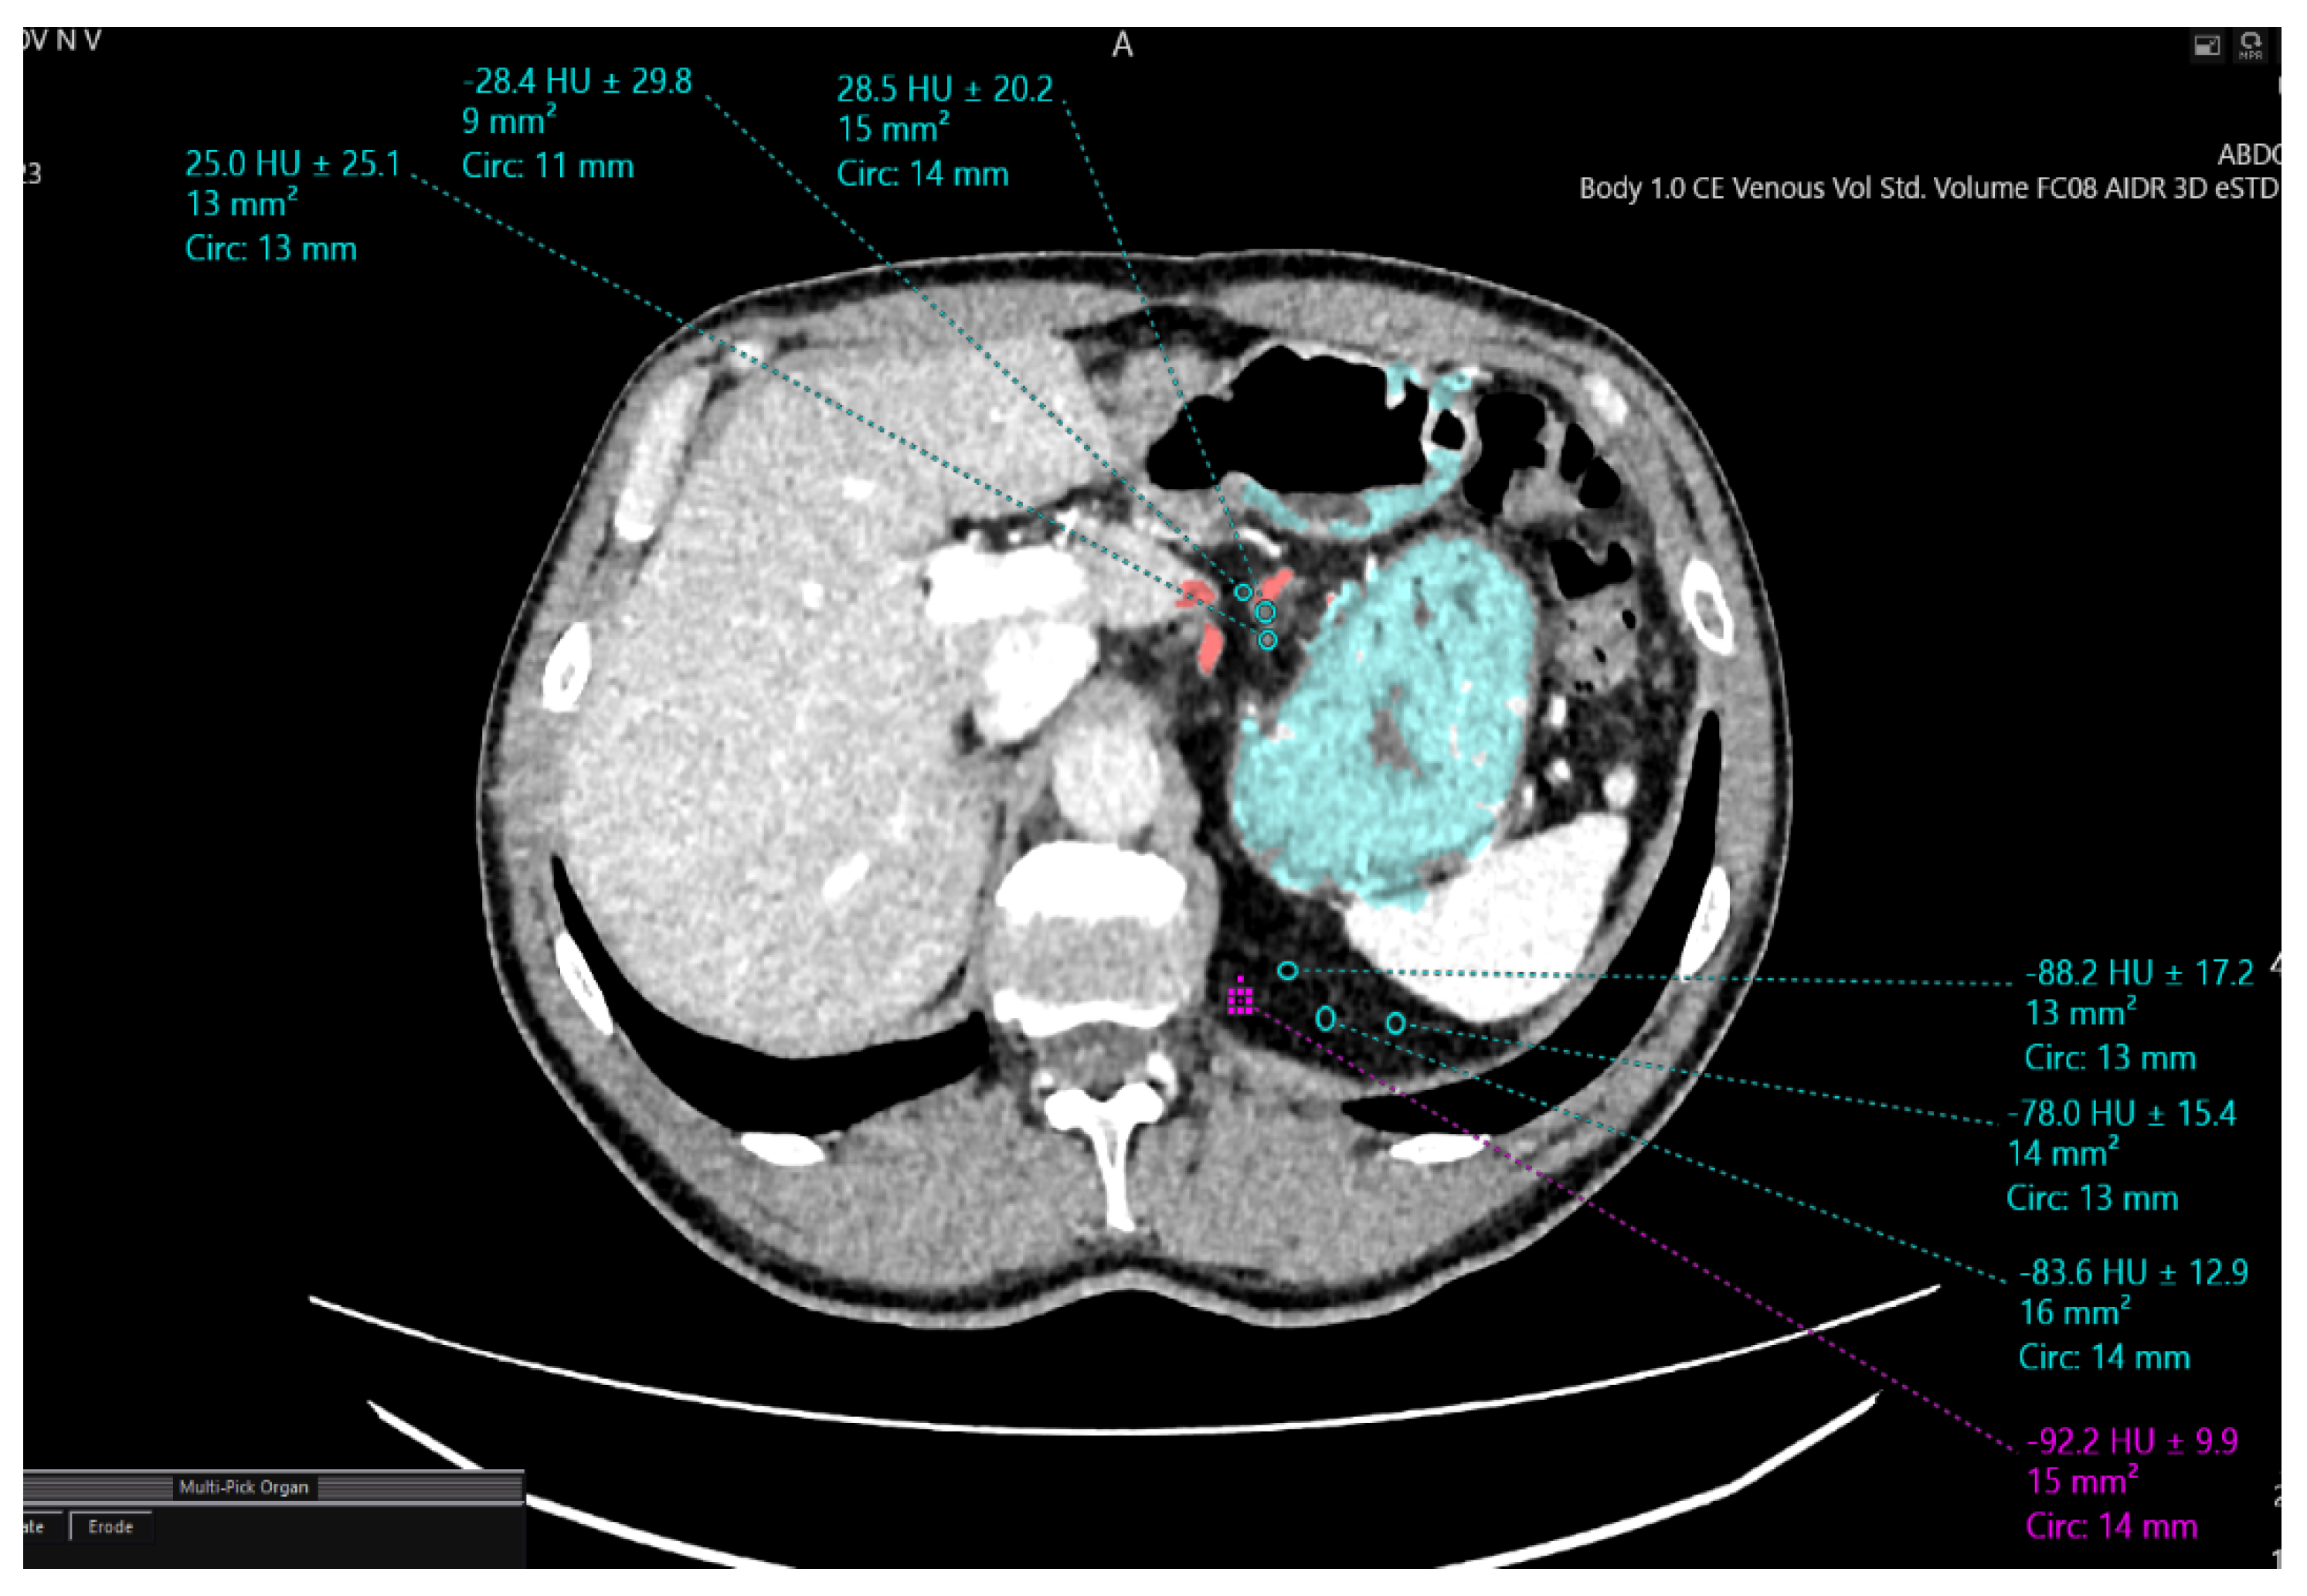

| Densitometric Density Points | Mesogastric Layer Along the Left Gastric Artery (HU) | Mesogastric Layer in the Region of Retrogastric Tissue (HU) |

|---|---|---|

| 1 | −88.2 | −28.2 |

| 2 | −78.8 | −26.6 |

| 3 | −92.9 | −27.7 |